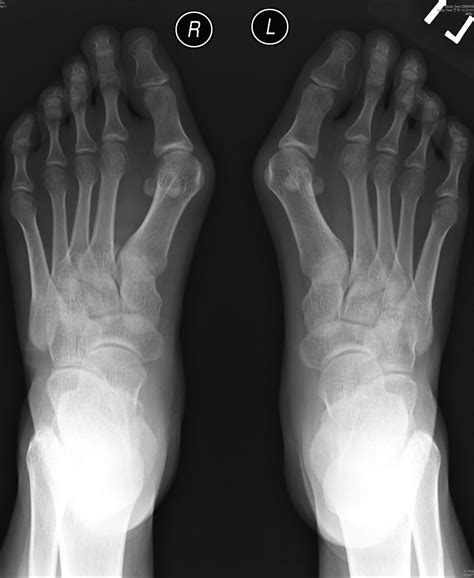

Hallux Valgus